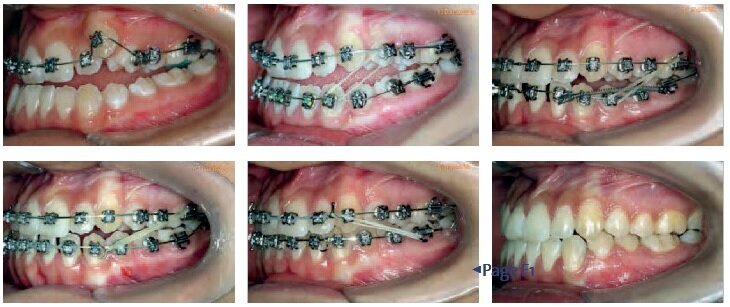

This patient, aged 15 years, was treated in 5 visits spread over 31 months.

These photos show the treatment stages and the intervals between appointments. A Damon System was used to treat this case of a Class III malocclusion, with incredible results observed in the teeth and facial features.